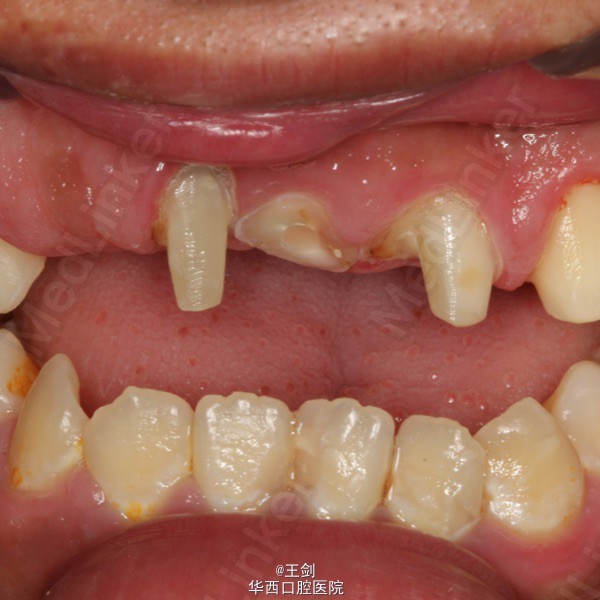

由于11牙正好位于中线,为保证修复效果,11牙作截冠处理,12牙残根纤维桩修复,并将12牙做成11牙的形态,最后做固定桥修复。图中显示牙体预备后正侧面观,可见前牙为反合状态,通过固定桥修复讲前牙关系改为切合。最后一图为戴暂冠后